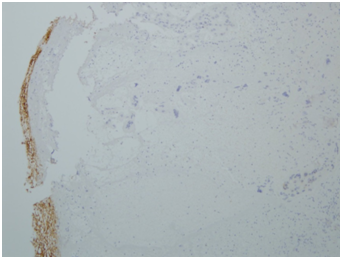

A specimen labeled as left frontoparietal hematoma - ? cavernoma from a 41 year old non-hypertensive female patient on ventilator was received for histopathologic examination. The patient was transferred from outside hospital to neurosurgical department of our hospital for craniotomy and evacuation of intracerebral hematoma. The clinoradiologic diagnosis was spontaneous intracerebral hematoma with intraventricular extension with normal ventricle, probably due to cavernoma. The microscopic examination of the specimen revealed extensive hemorrhage with peripherally placed mono-nucleated and multinucleated atypical cells. The mononucleotide cells were medium to large size with abundant cytoplasm and central large hyperchromatic nuclei. The multinucleated cells were large with abundant eosinophilic cytoplasm and hyperchromatic multinucleated bizarre nuclei. They were considered as cytotrophoblasts and syncytiotrophoblasts respectively (Figure 1-4). Immunohistochemistry showed that the atypical cells were CKAE1AE3 +, HCG+, GFAP-, CD31- and Vimentin- (Figure 5 to 10). A thin rim of GFAP positive glial tissue was seen in one fragment. Based on these findings, a diagnosis of metastatic choriocarcinoma was made. The patient survived the surgery and started recovering neurologically, but chose to go back to her own country for further management. So, we could not get any details of her obstetric history or previous medical illness.

Figure 1 Cytotrophoblasts.

Figure 5 CKAE1AE3.

Figure 6 CKAE1AE3.